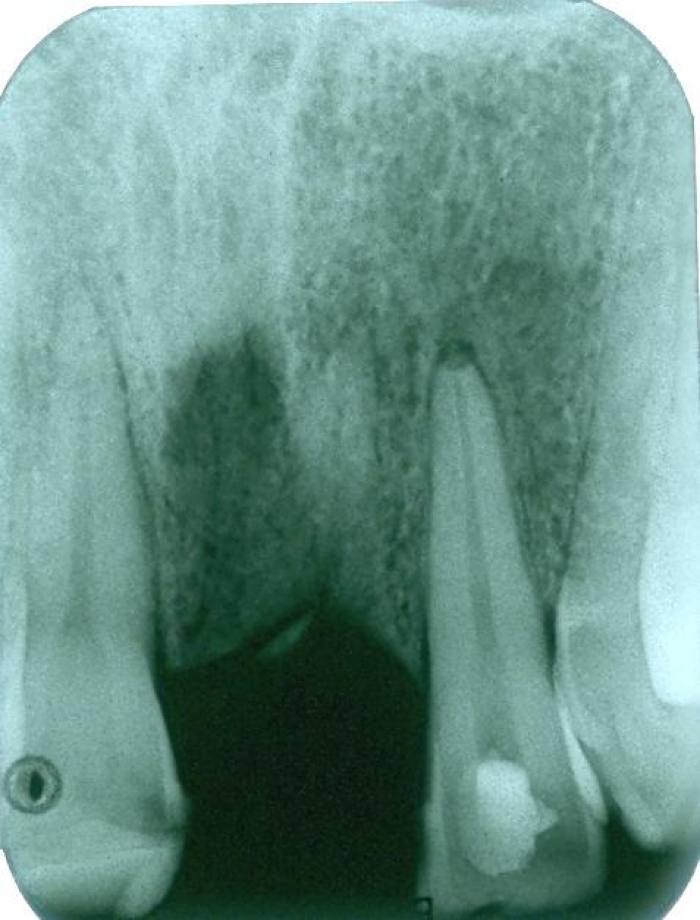

Raio X inicial